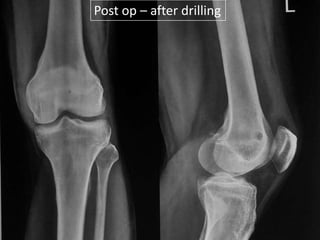

Post op – after drilling

CT – Guided Drilling

•

OPD procedure,

Localization of the nidus in CT Scan,

Local anesthesia,

K-wire passed into nidus,

Transferred to OT,

Short GA,

Drilling of the nidus by a cannulated drill,

Complete relief of pain.

Post op –after drilling

• 60.

CT – GuidedDrilling • • • • • • • • OPD procedure, Localization of the nidus in CT Scan, Local anesthesia, K-wire passed into nidus, Transferred to OT, Short GA, Drilling of the nidus by a cannulated drill, Complete relief of pain.